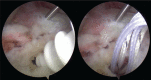

Arthroscopic techniques are considered the gold standard for treatment of displaced avulsion fractures of the anterior cruciate ligament. However, most arthroscopic surgical techniques and fixation methods are technically demanding and require removal of hard implant. This report describes a new, easy, safe, and all-arthroscopic method for reduction and fixation of displaced tibial intercondylar eminence fractures by using 1 anchor and 1 Pushlock.From January 2015 to June 2017, 8 adult patients with type II and III displaced tibial intercondylar eminence fractures were operated using this technique. Clinical assessment included patient demographics, cause of injury, delay before surgery, operation time, time to return to work and sport, International Knee Documentation Committee scores, and Lysholm knee scores.The average operation time was 48 minutes. The average follow-up period was 12.5 months. At the 6-month follow-up, all patients had acquired fracture union and complete functional recovery and were able to return to work. International Knee Documentation Committee objective scores and Lysholm knee scores were 92.4 (range 88-94) and 93.6 (range 90-96), respectively. At the last follow-up, anterior drawer, Lachman's test, and pivot shift tests were negative, and all patients had returned to their preinjury activity levels.Arthroscopic fixation by use of 1 anchor and 1 Pushlock is an easy, safe, and minimally invasive technique for treatment of displaced tibial intercondylar eminence fractures and does not require further surgery to remove fixation devices.Level of Evidence: Level IV, therapeutic case series.